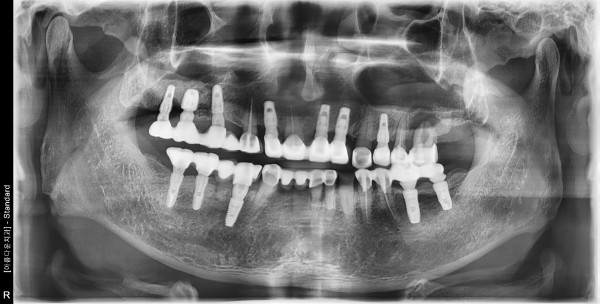

70세남자 좌측구치부 뼈이식및 임플란트식립